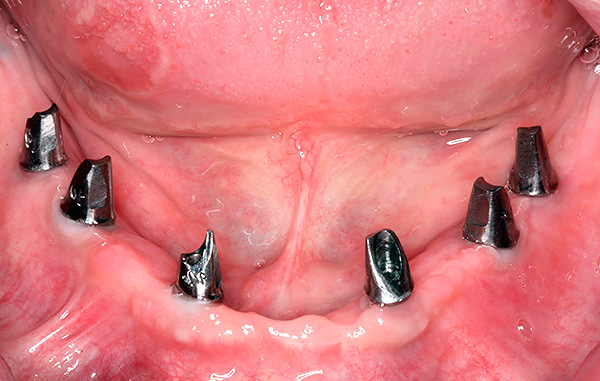

Os resultados das próteses usando a tecnologia All-on-4 parecem esteticamente agradáveis - exemplos são mostrados nas fotos a seguir.

Exemplo 2, foto antes do tratamento:

Depois:

A foto abaixo mostra um exemplo de aparência da dentadura ao usar as duas tecnologias - All-on-4 e All-on-6: